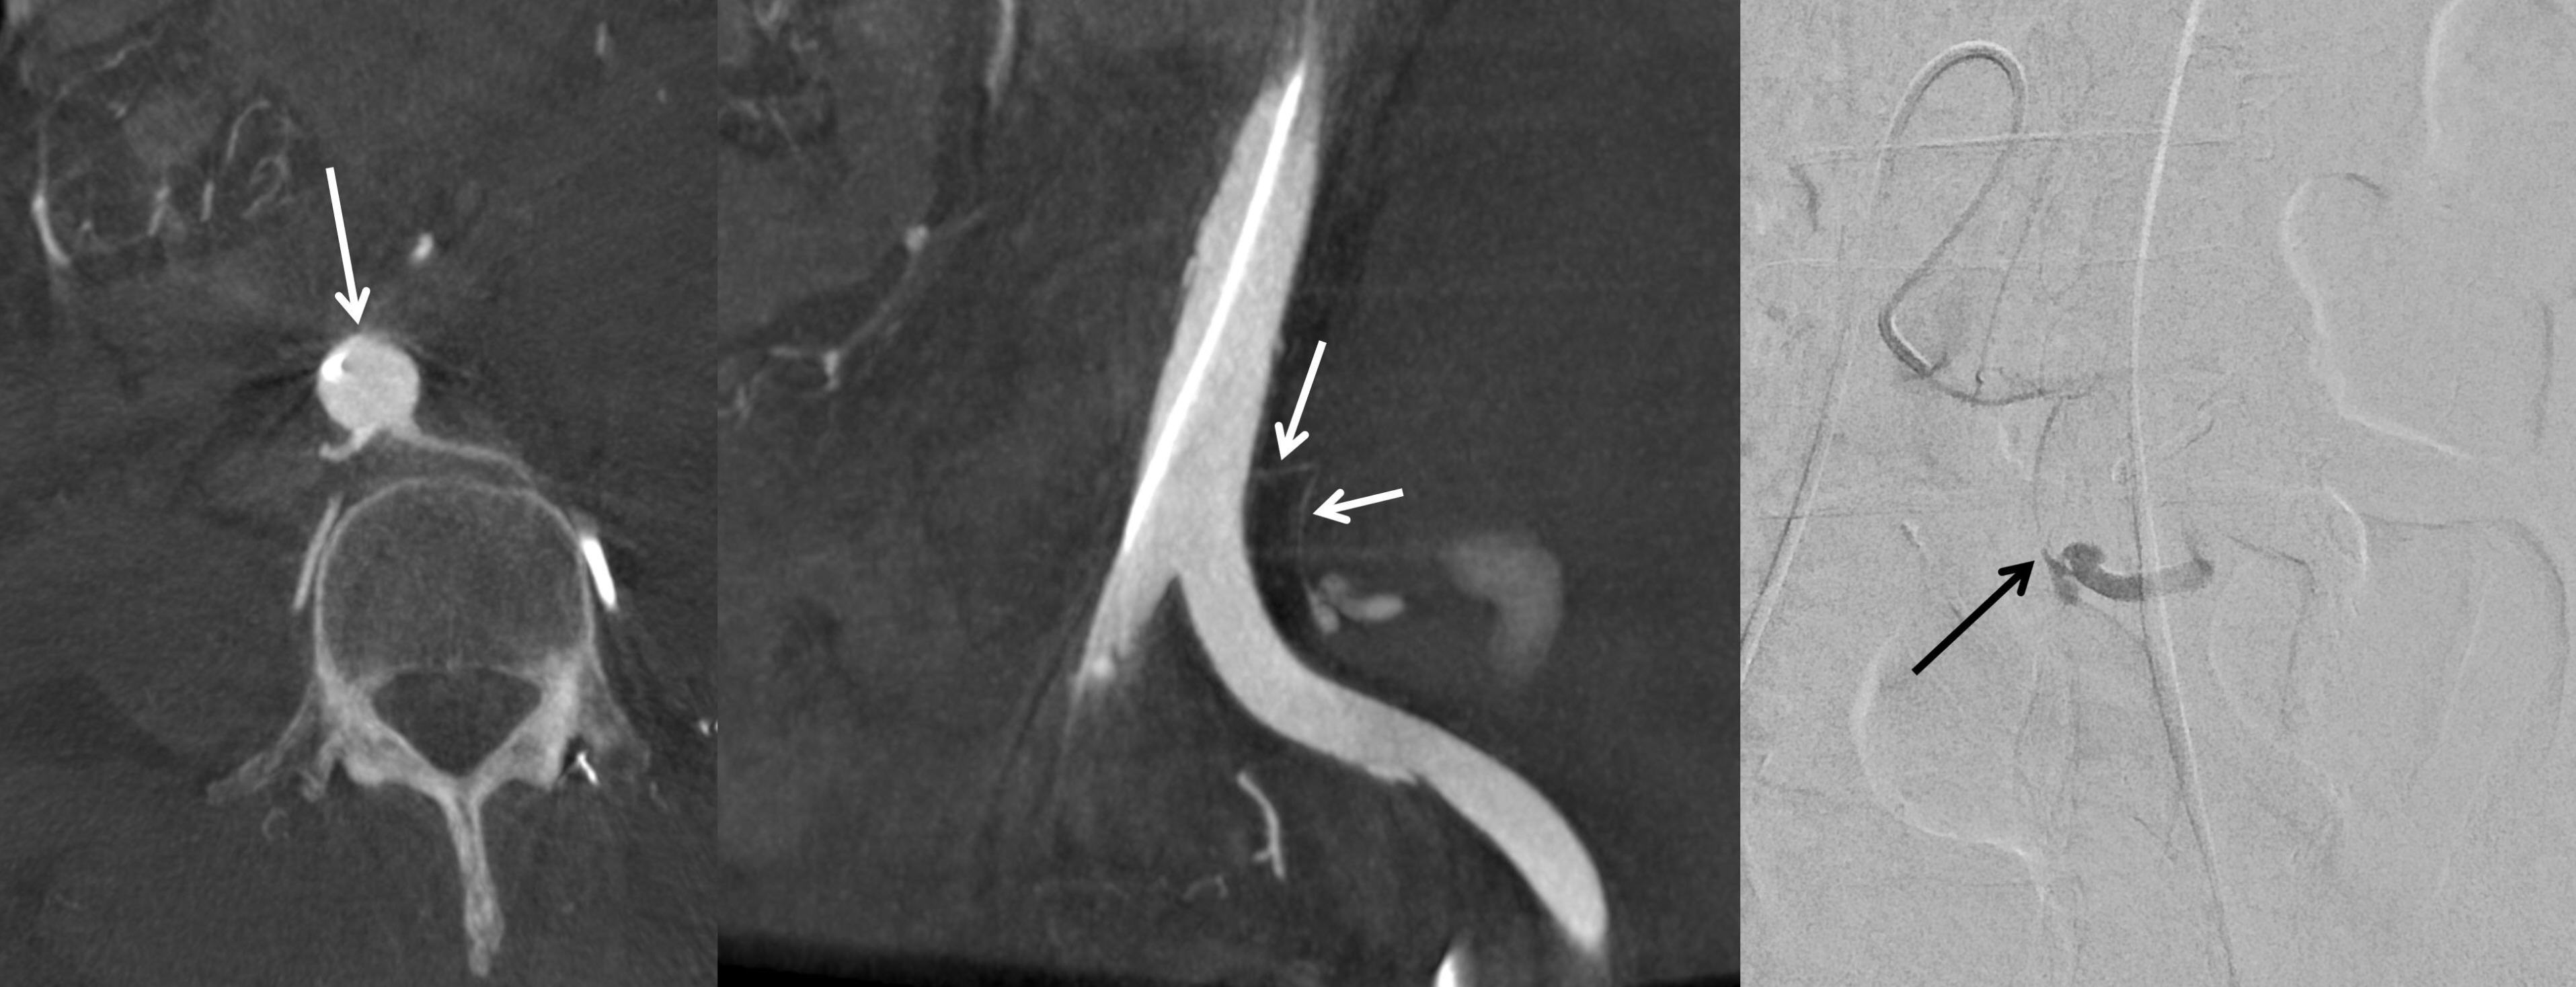

Axial cone-beam CT images revealed a thin artery arising at the 12 o’clock position from the infrarenal aorta, which coursed leftward toward the left ureter, made an L-shaped bend, and descended, with active bleeding observed (

Fig. 2). Based on these findings, selective catheterization of this artery was achieved using the 5-Fr diagnostic catheter (RH; Jungsung Medical, Seoul, Korea) and a 1.5-Fr microcatheter (Veloute Ultra, Asahi Intecc, Nagoya, Japan). Embolization was then performed using a 1:4 mixture of NBCA and ethiodized oil.

Fig. 2.Axial and coronal cone-beam CT images as well as angiographic image, obtained during the procedure, demonstrate a bleeding left ureteric artery (arrows) originating from the abdominal aorta in the 12 o’clock direction and coursing posterolaterally to the left before sharply angling into an L-shaped configuration.